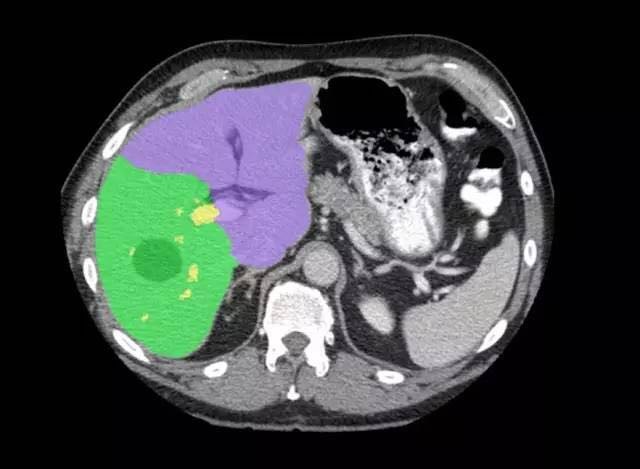

近日GE Revolution HD 精准能谱CT携手GE最新AW4.7后处理工作站在山东济南正式发布。和前款工作站相比,AW4.7功能更加强大,让圈内人不得不感叹GE在后处理软件技术的领先地位。 这台后处理站简直帅到没朋友: Hepatic VCAR 强大的VCAR系统,可见自动对肝脏进行分段,且对病灶及肝脏体积进行测量。外科医生一定非常喜欢这一功能。